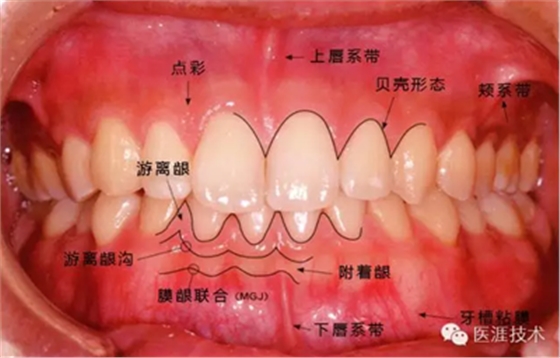

①健康、正常的牙周組織如何形成?

健康牙周組織的牙齦邊緣呈珊瑚粉,邊緣牙齦略呈圓弧狀。牙間可見三角形的牙間乳頭,牙齦邊緣相連呈貝殼形。

附著齦與游離齦相連時,有時有游離齦溝存在(成人的30~40%)。

附著齦通過膠原纖維牢固結(jié)合骨骼與牙骨質(zhì),因此可見不可動、硬而緊繃的點彩(橘皮樣點狀凹凸)。

從牙齦牙槽粘膜到根尖有牙槽粘膜。牙槽粘膜為暗紅色,與骨骼結(jié)合較松,故可動。

健康且正常的牙周組織臨床圖像